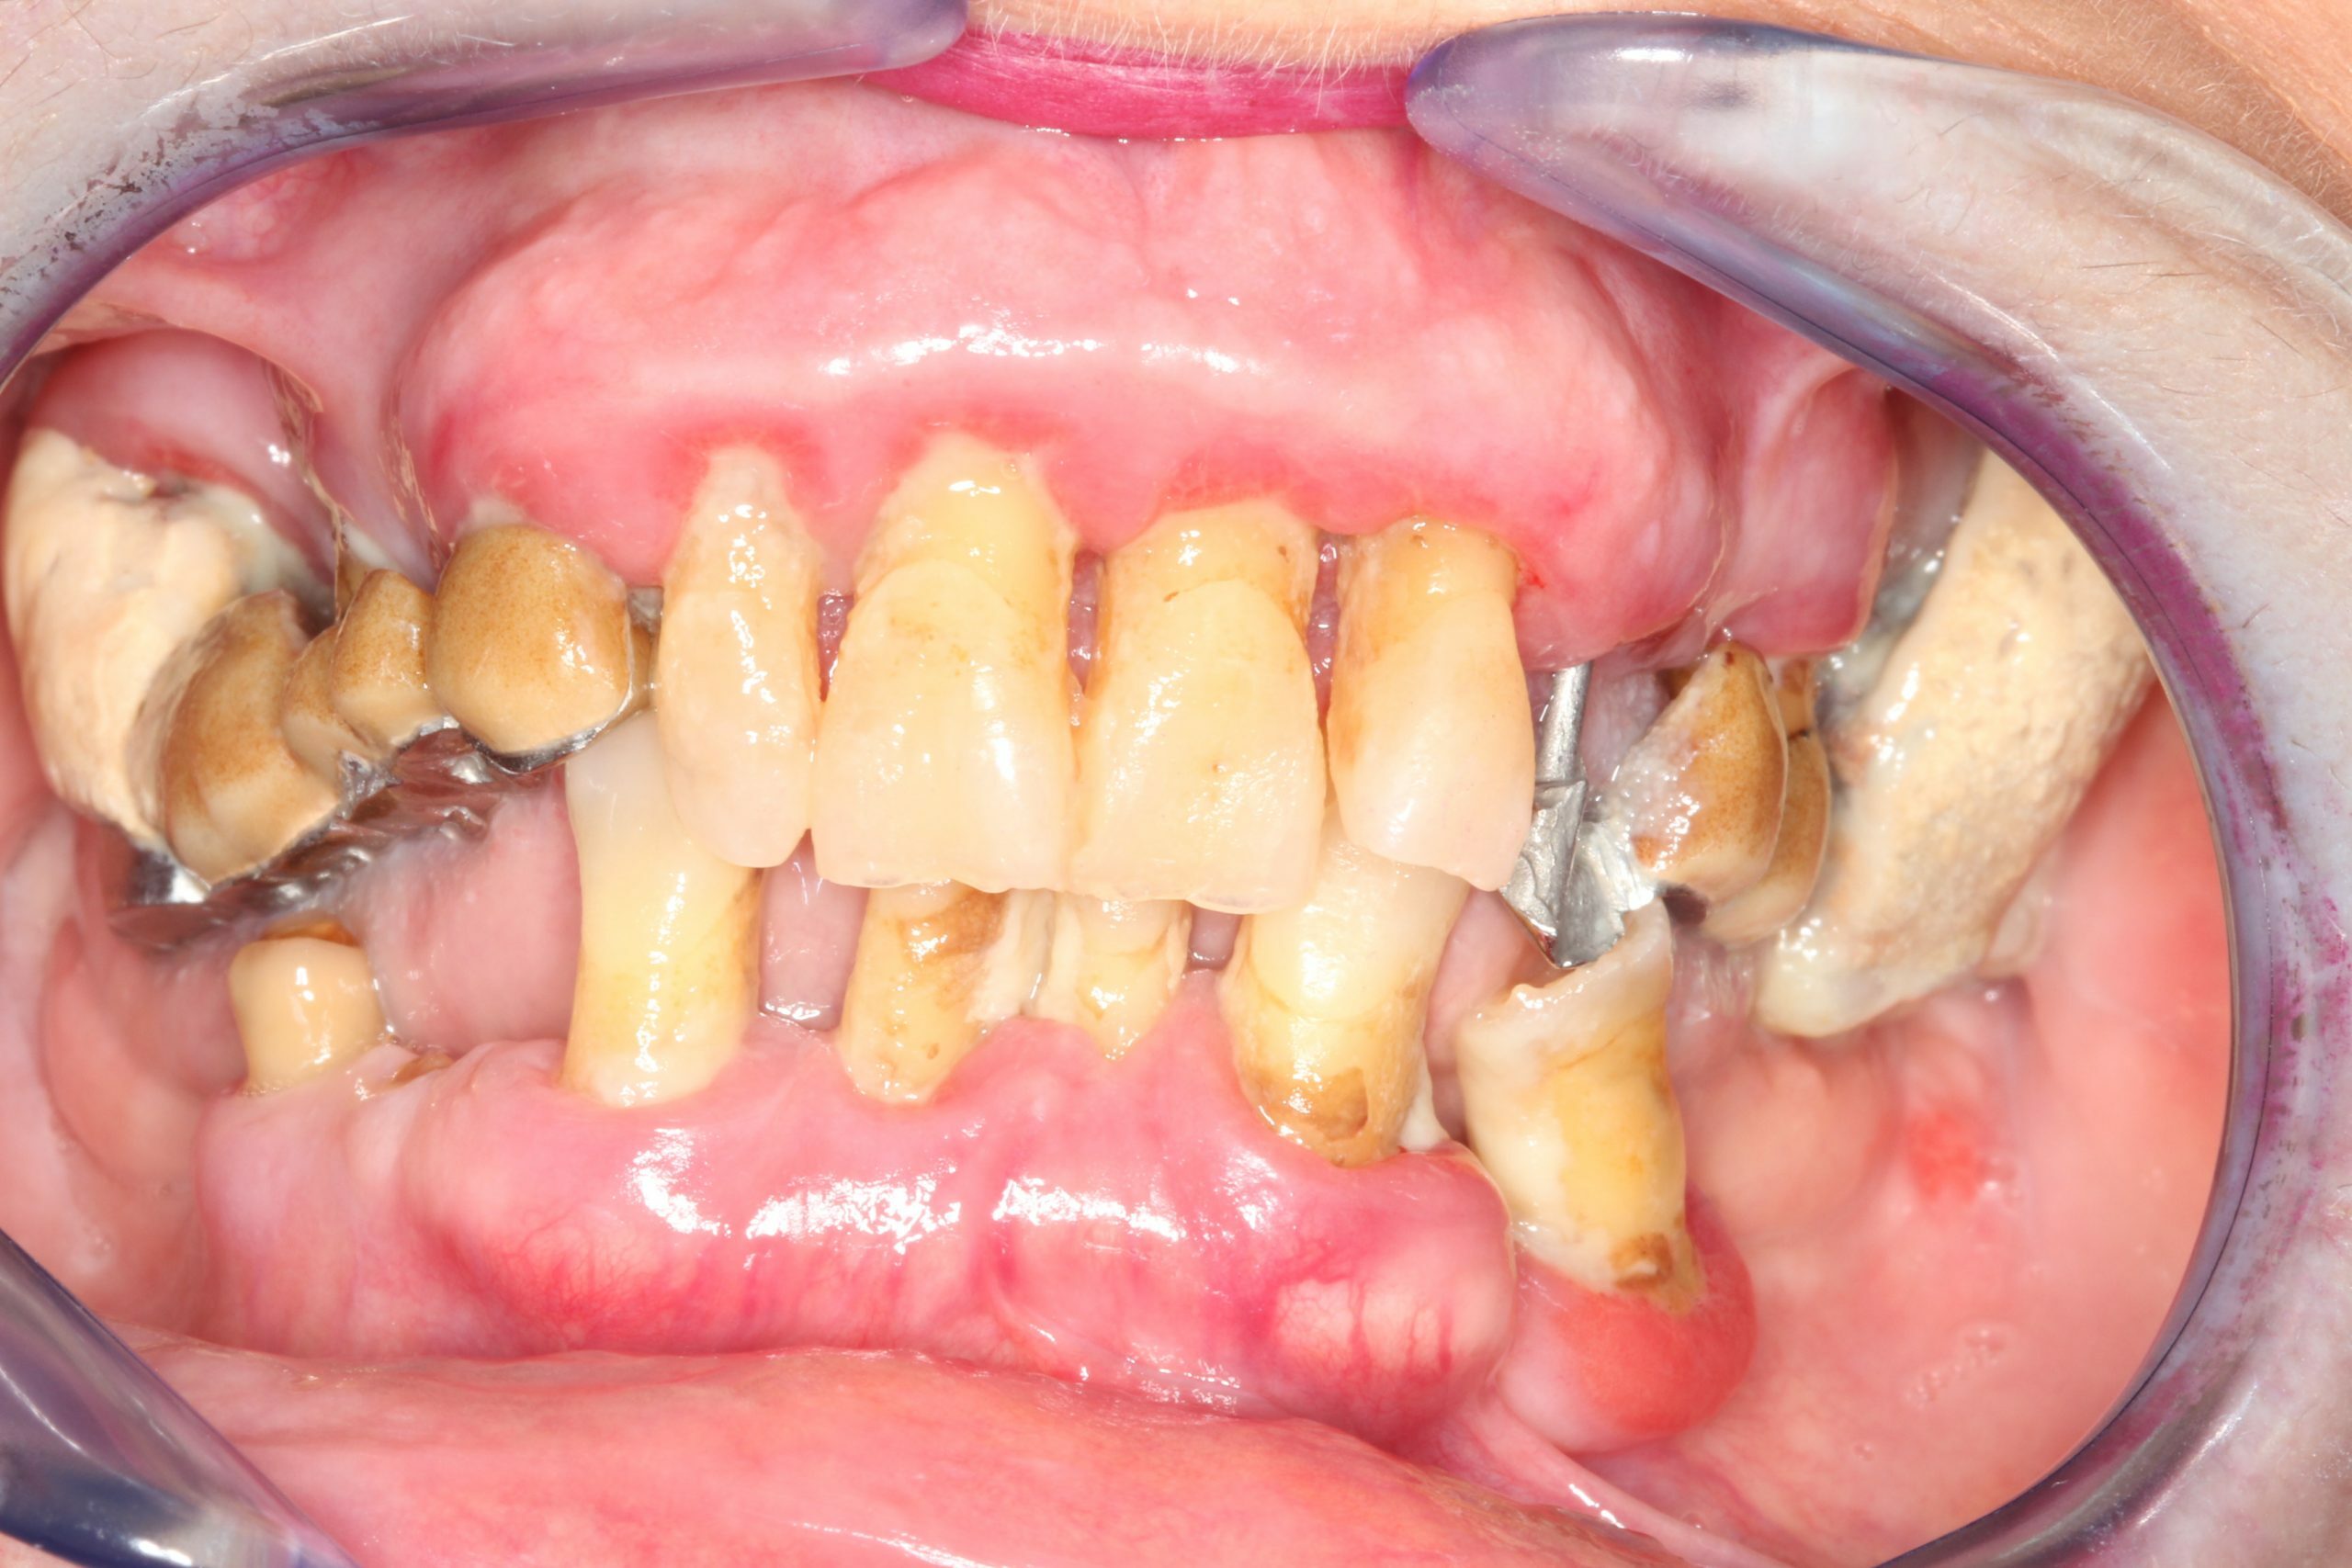

El éxito de la implantología depende de la existencia de hueso adecuado para soportar el implante. La pérdida dental a menudo causa reabsorción ósea. Diagnosticamos Defectos Óseos Parciales o Afecciones Avanzadas y Crónicas que requieren reconstrucción ósea generalizada. La planificación virtual es indispensable.

Casos de Éxito: Experiencia que Genera Confianza

Nuestra experiencia se centra en la implantología compleja y la regeneración ósea, logrando rehabilitaciones dentales estables y duraderas con el máximo rigor médico.